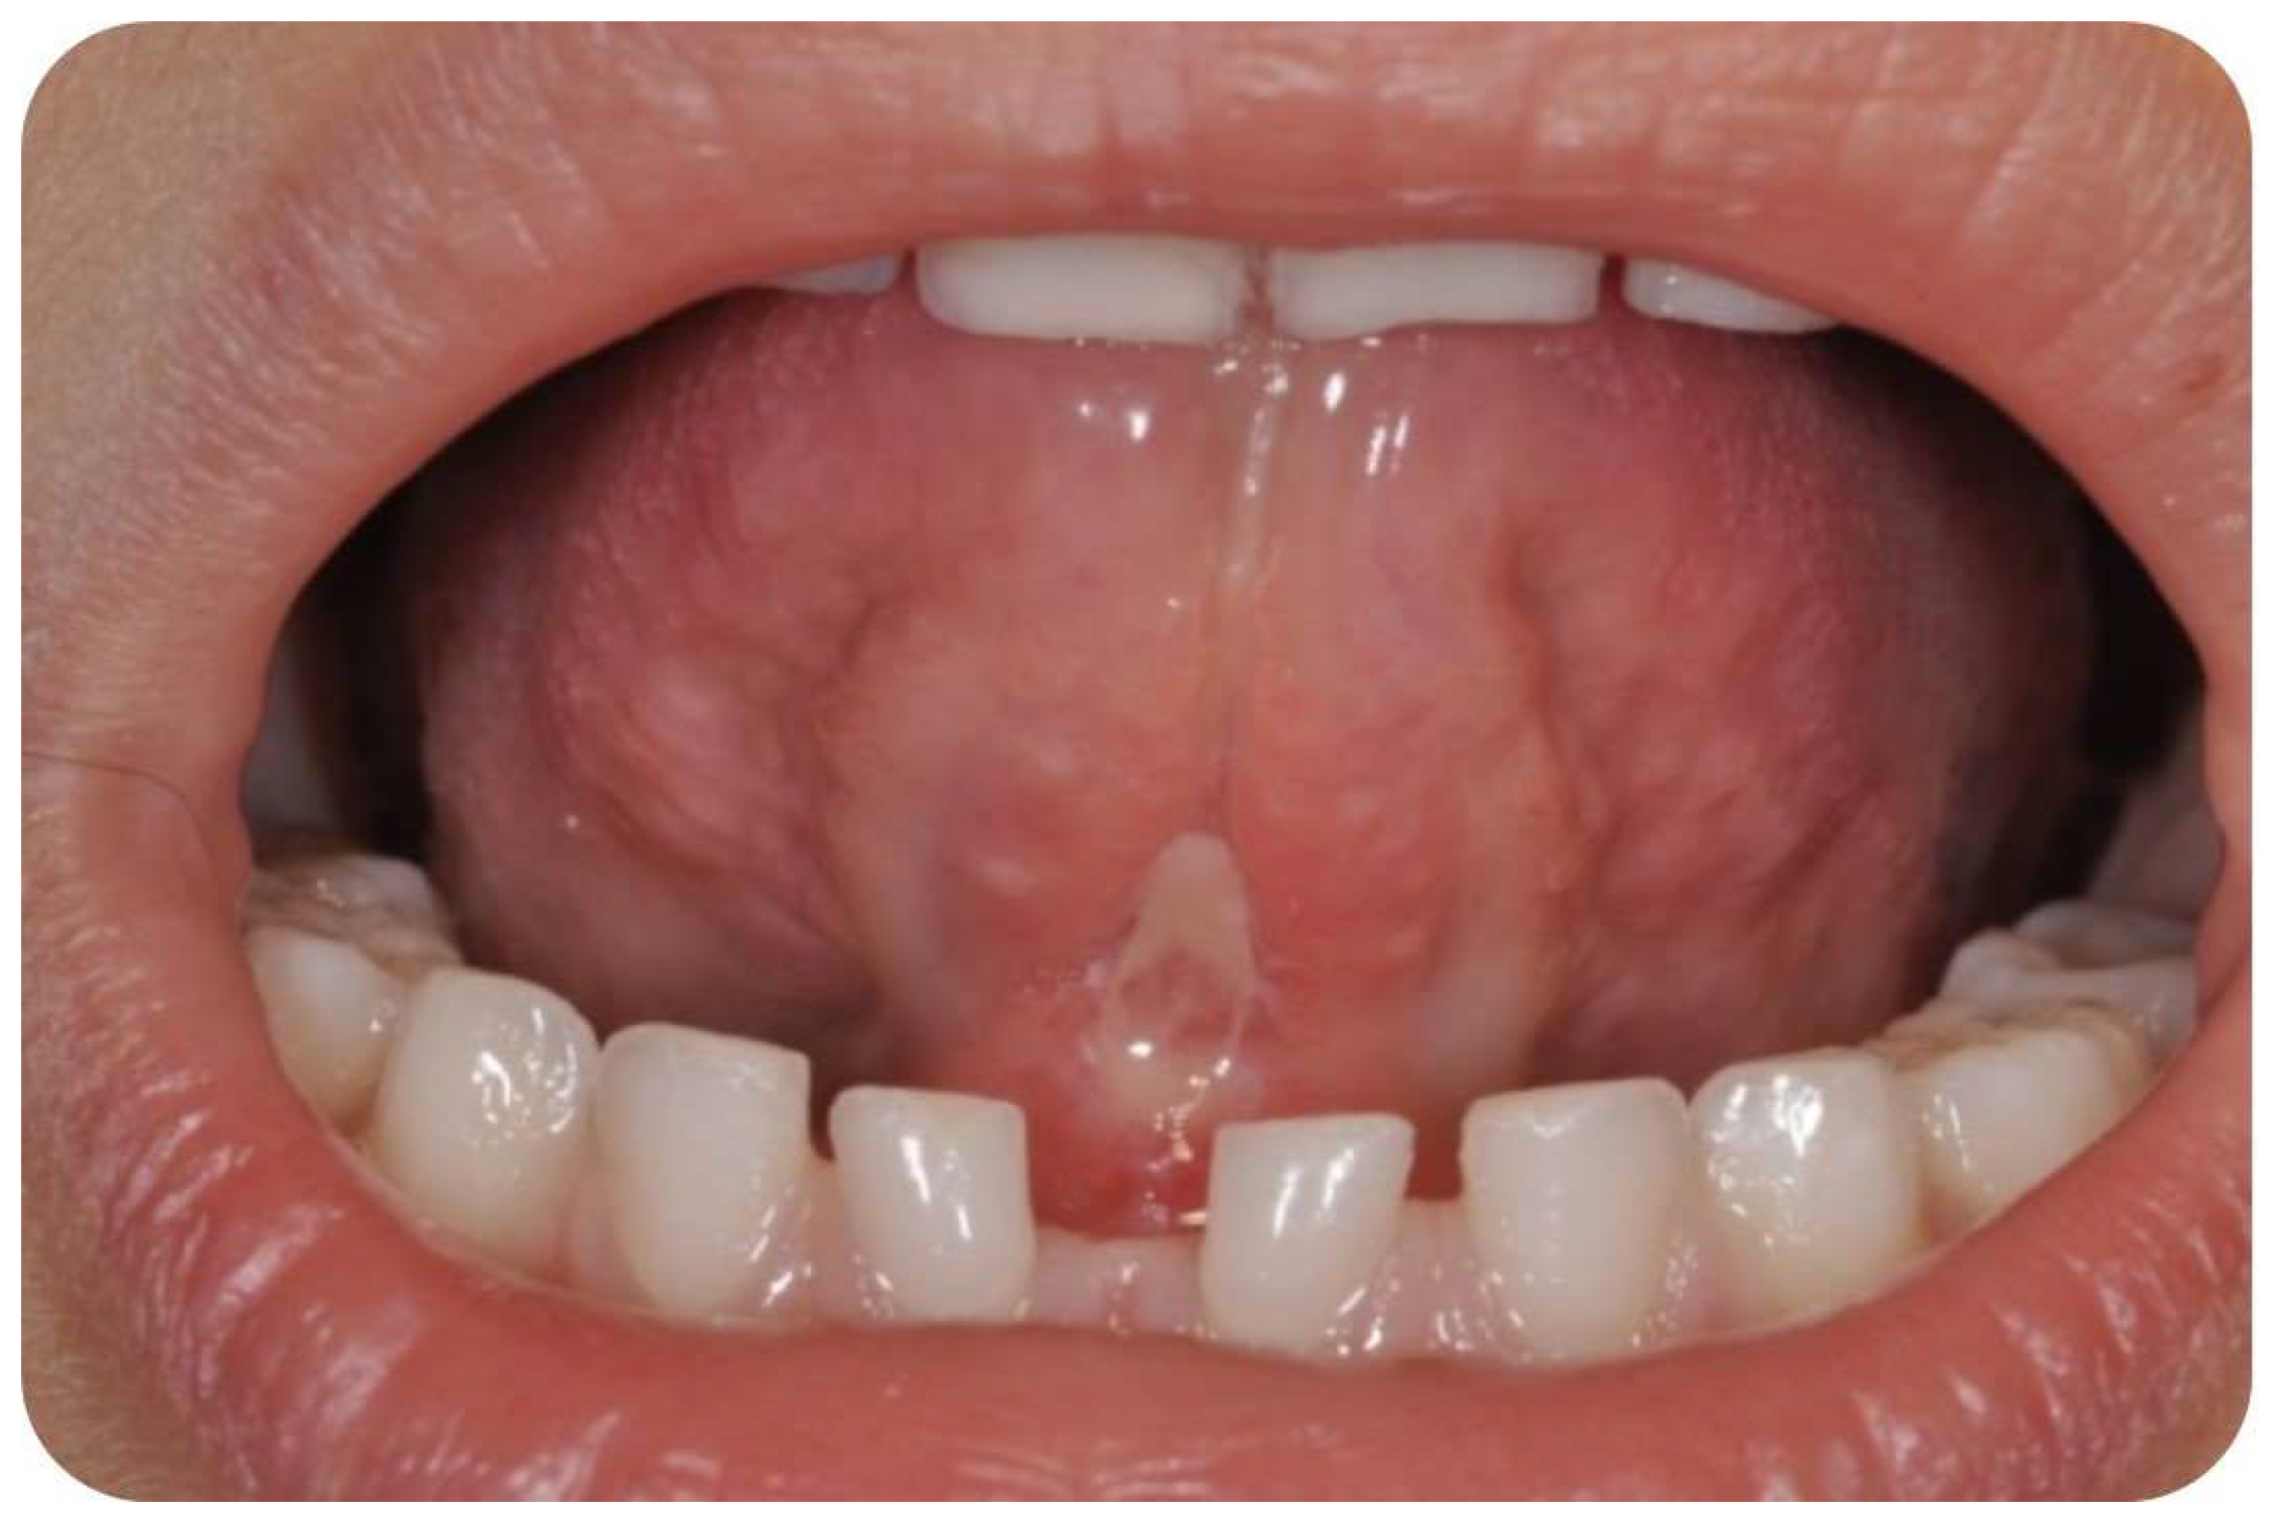

1. Introduction

2. Materials and Methods

2.3. Surgical Procedure